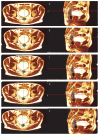

Materials and methods: For this prospective pilot study, patients diagnosed with locally advanced rectal cancer (LARC) with positive lymph node clinical staging underwent SMART on rectal lesion and mesorectum using hybrid MR-Linac (MRIdian ViewRay). Dose prescription at 80% isodose for the rectal lesion and mesorectum was 40 Gy (8 Gy/fr) and 25 Gy (5 Gy/fr), respectively, delivered on 5 days (3 fr/week). Response assessment by MRI was performed 3 weeks after SMART, then patients fit for surgery underwent total mesorectal excision. Primary endpoint was evaluation of adverse effect of radiotherapy. Secondary endpoint was pathological complete response rate. Early toxicity was graded according to the Common Terminology Criteria for Adverse Events (CTCAE v5.0).

Results: From October 2020 to January 2022, twenty patients underwent rectal SMART. No grade 3-5 toxicity was recorded. Twelve patients were eligible for total mesorectal excision (TME). Mean interval between the completion of SMART and surgery was 4 weeks. Pathological downstaging occurred in all patients; rate of pathological complete response (pCR) was 17%. pCR occurred with a prolonged time to surgery (> 7 weeks).